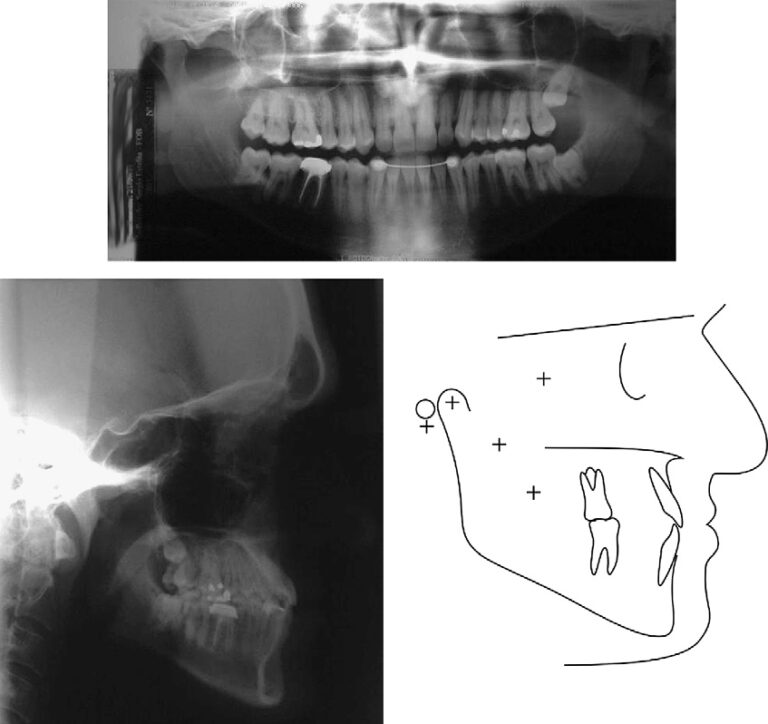

The patient was a man (age, 23 years 11 months) with a Class III subdivision left malocclusion with negative overjet and facial imbalance. His chief concerns were his anterior crossbite and lower lip protrusion. His parents had no Class III characteristics. The facial photographs showed a prognathic mandible and a Class III appearance (Fig 1). The patient could close his lips without mentalis strain, but he was self-conscious about the way his teeth occluded and the appearance of his teeth. The pretreatment intraoral photographs and dental casts show a Class III subdivision malocclusion with Class I on the right and Class III on the left (Figs 1 and 2). There was good alignment of the mandibular incisors, and all teeth were present including the third molars (Fig 3, A). Cephalometrically, he had maxillary retrusion, slight mandibular protrusion, and a balanced facial pattern, with the exception of excessive lower anterior face height. The maxillary incisors were bucally tipped and protruded, and the mandibular incisors were lingually tipped and retruded. He had an acute nasiolabial angle (Fig 3, B and C; Table).

Fig 3. Pretreatment panoramic and cephalometric radiographs and tracing.

Co-A, Condylion to A-point; A-Nperp, A-point to nasion-perpendicular; Co-Gn, condylion to gnathion; P-Nperp, pogonion to nasion-perpendicular;

LAFH, lower anterior face height, from anterior nasal spine to menton; Mx1.NA, maxillary incisor long axis to NA angle; Mx1-NA, most anterior

point of crown of maxillary incisor to NA line; Mx1.PP, maxillary incisor long axis to palatal plane angle; Mx1-PP, perpendicular distance between

incisal edge of maxillary central incisor and palatal plane; Md1.NB, mandibular incisor long axis to NB angle; Md1-NB, most anterior point of crown

of mandibular incisor to NB line; Mx6-PP, perpendicular distance between mesial cusp of maxillary first molar and palatal plane; Md1-GoMe, perpendicular

distance between incisal edge of mandibular incisor and mandibular plane; nasolabial angle, angle formed by the most anterior point on

the upper lip to a line from subnasion to columella; upper lip to S line, from the most anterior point on the upper lip to a plane from the center of the

S-shaped curve between the tip of the nose and the skin subnasale to the soft-tissue pogonion; lower lip to S line, from the most anterior point on the

lower lip to a plane from the center of the S-shaped curve between the tip of the nose and the skin subnasale to the soft-tissue pogonion.